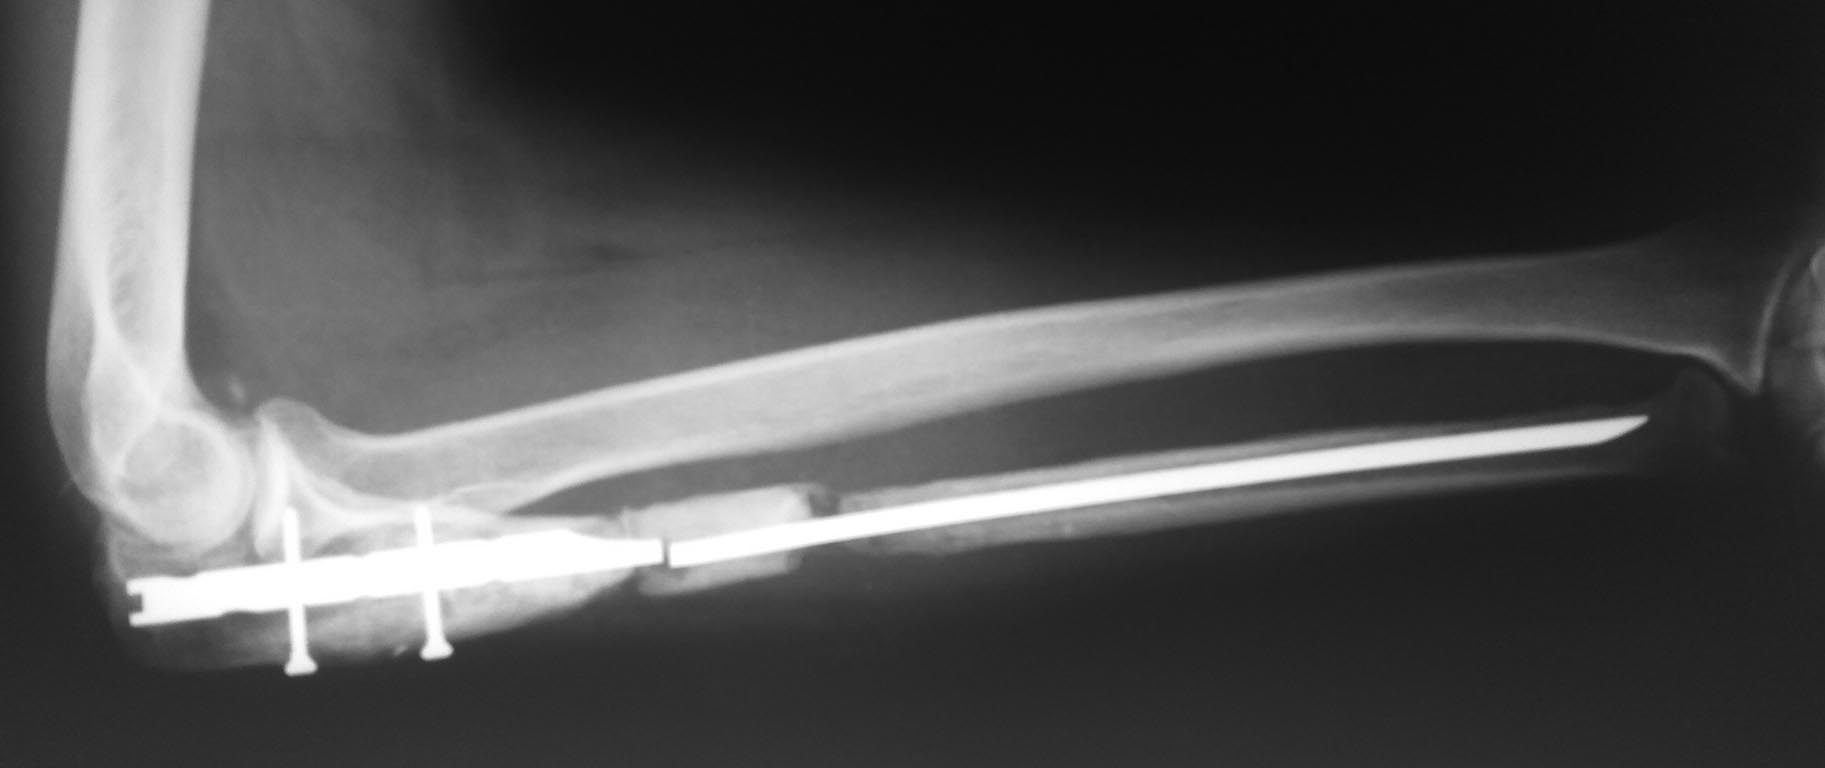

Ложный сустав локтевой кости

Коротко анамнез: соматически здоров, работает сварщиком, поступил в плановом порядке по анализам все в пределах нормы. Травма получена в 2013г. На протяжении 3-х лет оперирован 3-х кратно( накостно с последующими накостными реостеосинтезами, с однократной пластикой по Хахутову) Консолидации не получено. В 2016г. обратился в нешу больницу, выполнен накостный реостеосинтез с резекцией зоны ложного атрофического сустава, костной аутопластикой м/берцовой кости.( снимков увы с пластиной не нашел) Через 6 мес. выявлена картина нестабильности проксимальной фиксации , в связи с чем, малоинвазивно удалена пластина и выполнен БИОС локтевым штифтом( есть только такой вариант). Спустя 5 мес. пациент отметил щелчок в области предплечья , контрольные снимки предоставляю. Хотелось бы услышать мнение компетентных спецов, кто сталкивался с такой проблемой, потому как на месте мнения по опер.тактике расходятся и надо все окончательно взвесить и принять решение.

Наши варианты: 1) закрыто удалить штифт. , Выполнить косую остеотомию локтевой кости в н/3, вновь выполнить фиксацию перелома таким же штифтом. Дополнить все аппаратом Илизарова из 3-х баз для возможной компрессии на уровне ложного сустава.

2) Учитывая срок после операции, картину атрофического ложного сустава, удалить металлоконструкцию, убрать нежизнеспособный трансплантант, освежить концы отломков , вновь выполнить аутопластику м/берцовой кость, дополнить из крыла подвздошной кости. Фиксация в аппарате Илизарова.